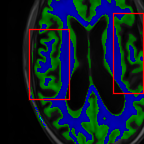

Sparsity LI 2D CNN 3D CNN Ours GT

4 Refer to caption (a) 0.6787/0.7972 Refer to caption (b) 0.8143/0.8776 Refer to caption (c) 0.8190/0.8714 Refer to caption (d) 0.8664/0.9085 Refer to caption (e) GM/WM

Refer to caption (f) 0.6808/0.7161 Refer to caption (g) 0.8103/0.8631 Refer to caption (h) 0.7950/0.8606 Refer to caption (i) 0.8598/0.9115 Refer to caption (j) GM/WM

8 Refer to caption (k) 0.5139/0.7240 Refer to caption (l) 0.6619/0.8224 Refer to caption (m) 0.6878/0.8584 Refer to caption (n) 0.7798/0.8853 Refer to caption (o) GM/WM

Refer to caption (p) 0.5910/0.6947 Refer to caption (q) 0.6516/0.8021 Refer to caption (r) 0.6507/0.8186 Refer to caption (s) 0.7471/0.8540 Refer to caption (t) GM/WM

Figure 6: Visual comparison of gray matter (Green)/white matter (Blue) segmentation over different methods, with respective DICE scores listed under the images.

In Fig. 6, we demonstrate the advantage of the proposed method in brain matter segmentation. It is clear that although 2D and 3D CNN generates visually plausible interpolation as presented in Fig. 5, the brain matters are easily misclassified due to incorrect anatomical structures and blurred details.